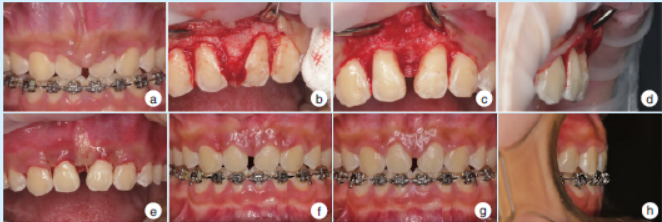

4. 治疗及结果

牙周基础治疗后行牙周骨成形术及牙龈成形术。术后2 周及2 个月复查无不适,12、22 牙龈色形质良好,形态正常,唇侧牙槽骨基本正常(图3)。术后半年复查显示12、22 间牙龈及牙槽骨形态稳定,未见增生复发(图4)。

图3 正畸治疗致12、22间唇侧骨性凸起采用牙周骨成形术及牙龈成形术治疗